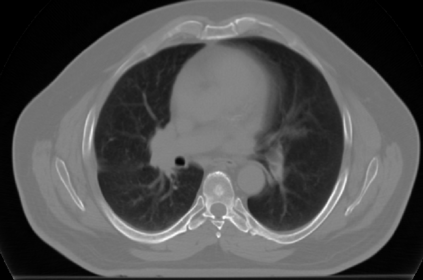

The COVID-19 pandemic has had a considerable impact on day-to-day life. Tackling the disease by providing the necessary resources to the affected is of paramount importance. However, estimation of the required resources is not a trivial task given the number of factors which determine the requirement. This issue can be addressed by predicting the probability that an infected patient requires Intensive Care Unit (ICU) support and the importance of each of the factors that influence it. Moreover, to assist the doctors in determining the patients at high risk of fatality, the probability of death is also calculated. For determining both the patient outcomes (ICU admission and death), a novel methodology is proposed by combining multi-modal features, extracted from Computed Tomography (CT) scans and Electronic Health Record (EHR) data. Deep learning models are leveraged to extract quantitative features from CT scans. These features combined with those directly read from the EHR database are fed into machine learning models to eventually output the probabilities of patient outcomes. This work demonstrates both the ability to apply a broad set of deep learning methods for general quantification of Chest CT scans and the ability to link these quantitative metrics to patient outcomes. The effectiveness of the proposed method is shown by testing it on an internally curated dataset, achieving a mean area under Receiver operating characteristic curve (AUC) of 0.77 on ICU admission prediction and a mean AUC of 0.73 on death prediction using the best performing classifiers.